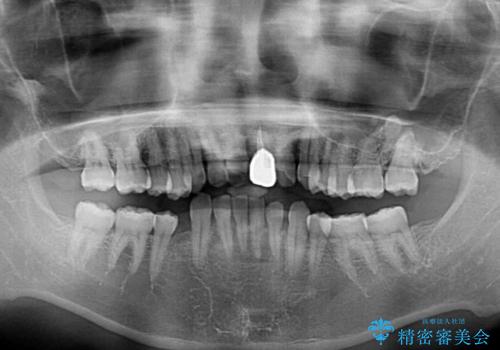

下顎は左右1本ずつ小臼歯が欠損しており、右側にはやや大きな欠損がありました。

欠損により下顎歯列は相対的に小さく、上顎に深く咬みこんでしまうディープバイトとなっていました。

インビザラインによる治療を希望されたため、左側のスペースは閉じ、右側はスペースをより拡大し、インプラント補綴を行うこととしました。

咬合力が強く、インビザラインのみではディープバイトを改善することができず、半年間ほどワイヤー装置による矯正治療を行いました。

インプラントの埋入は矯正治療中に行い、矯正治療後はインプラント上補綴および、前歯のセラミック治療を行いました。